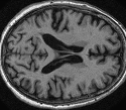

Looking at sample synthetic PET images in Fig. 3, it can be seen that all of the models are able to make reasonable predictions. The outputs of the U-PET and U-PET (no att.) look very similar and are smoothed compared to the input. The pix2pix predicts more details, which seem to be important for the discriminator. However, even though this model has finer predictions, the intensity values are worse compared to the U-PET and U-PET (no att.) as seen in Fig. 2; an example is given in Fig. 3 in the second row.

From a clinical perspective, the synthetic generated PET show a smoother version of the real PET images but keep the same pattern of FDG uptake, especially, hypometabolism in the respective brain areas. This backs up our hypothesis, that MRI contains information that correlates with the functional information of PET images. Moreover, the synthetic PET could be used as complementary visualization for physicians beyond the task of classification.

| MRI | PET | Synthetic PET | AttMap skip | AttMap |

In Fig. 4, the attention maps of the U-PET are shown for multiple examples. On the one hand, the attention map of the skip connection (AttMap skip) highlights details of the brain structure, which is in agreement with the assumption that the network has to transform the specific structures of the MRI scan into the PET modality. On the other hand, the attention gates used for the classification task rather focus on more specific regions. One can observe a trend that the attention maps used for classification tend to highlight regions which have a low uptake in the PET. Since areas with a lower uptake in the PET correspond to areas with lower functional activity (hypometabolism), this focus area of the network seems reasonable with respect to the classification task.